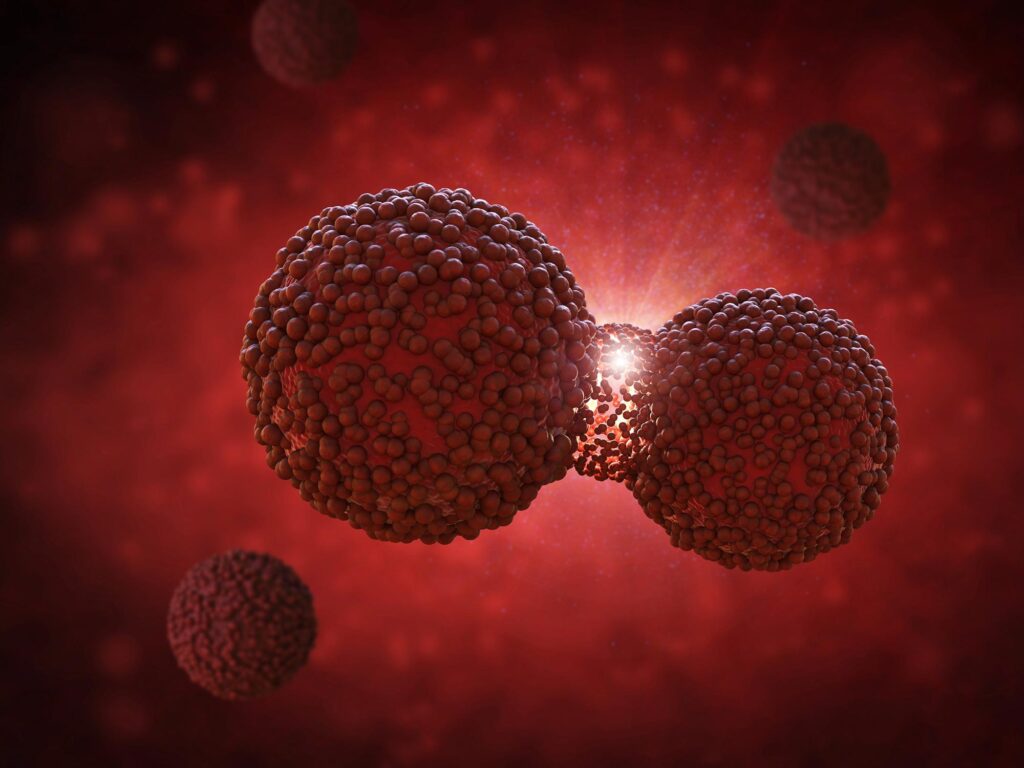

מחקר הוכיח את הקשר בין תרופות פופולריות לסוכרת לסרטן בלוטת התריס

מחקר סקנדינבי גדול על ידי Karolinska Institutet מראה כי אנלוגים של GLP-1, המשמשים בטיפול בסוכרת והשמנת יתר, אינם מגבירים את הסיכון לסרטן בלוטת התריס, מה שמאשר את בטיחותם במשך כמעט ארבע שנים של תצפית. מחקר מקיף של מכון קרולינסקה לא מצא ראיות לכך שאנלוגים של GLP-1 מגבירים את הסיכון לסרטן ...